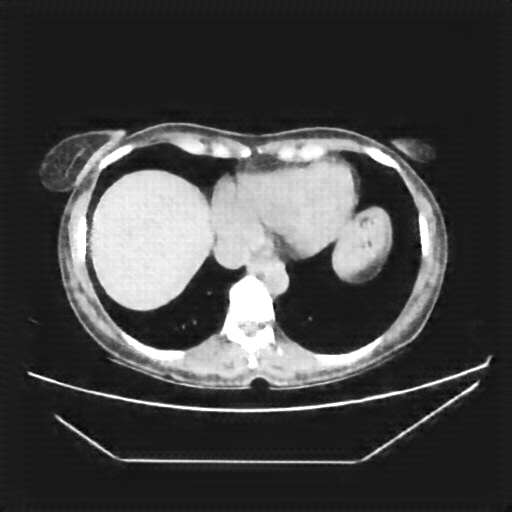

Reconstructed NATIVE CT scan (cycle consistency)

Full window (WL 1023.5, WW 4095 β†’ Low βˆ’1024, High +3071)

Original VENOUS CT scan

Generated VENOUS CT scan (A→B translation)